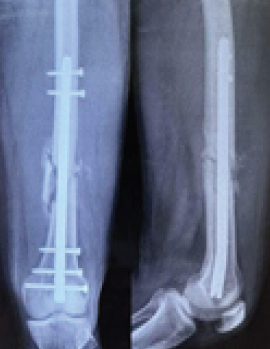

Figure 2: Anteroposterior and lateral views at 1.5 months showing distal third fracture of the femur with retrograde nail.

Out of all study participants, 58 patients had closed fractures and rest 2 patients had compound fractures. The mean operation-injury interval was 5.5 ± 0.67 days for antegrade nailing and 5.8 ± 0.65 days for retrograde nailing. The mean duration of the surgery was 85 ± 2.15 min for retrograde nailing and 95 ± 1.39 min for antegrade nailing. Mean time for radiological union with retrograde nailing was 10 ± 0.38 weeks (Fig. 1, 2, 3, 4) and with antegrade nailing, it was 14 0.44 weeks (Fig. 5, 6).